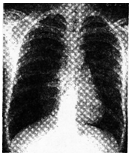

男,26岁。举重物时突发胸痛,进行性呼吸困难急诊就诊。既往体健。胸片如图,右肺中、

外带无肺纹理。

C.20 ml

D.40 ml

63.【答案】B

【解析】举重物时突发胸痛,进行性呼吸困难,右肺无肺纹理,既往体健,考虑气胸。气胸时语颤减弱或消失。

64.【答案】D

【解析】气胸发生时最佳的治疗措施为排气治疗:胸腔穿刺抽气、胸腔闭式引流。